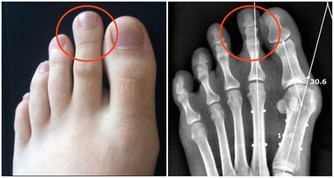

目前,患痛風的人越來越多,尤其是很多年輕人,不健康的生活習慣導致尿酸值越來越高,痛風發作的時候嚴重影響生活質量。然而,很多的痛風患者只是在盲目的降尿酸,並沒有弄清楚自己的尿酸為什麼會高,

如果你生活健康,沒有大量攝取啤酒、動物內臟、海鮮、濃茶等,最後尿酸值還是居高不下,還有一個重要的原因是——藥物性痛風,即很多藥物能夠導致尿酸高,今天就讓我們一起了解一下。